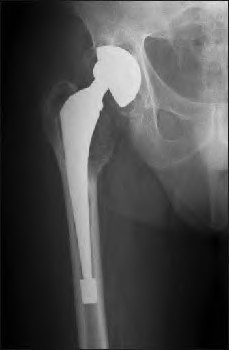

A 72-year-old female falls and sustains a periprosthetic femur fracture around her cementless total hip arthroplasty. Radiographs reveal a fracture extending just distal to the tip of the stem. The stem is radiographically loose, but there is excellent proximal and distal bone stock. According to the Vancouver classification, what is the fracture type and the recommended surgical treatment?

Explanation